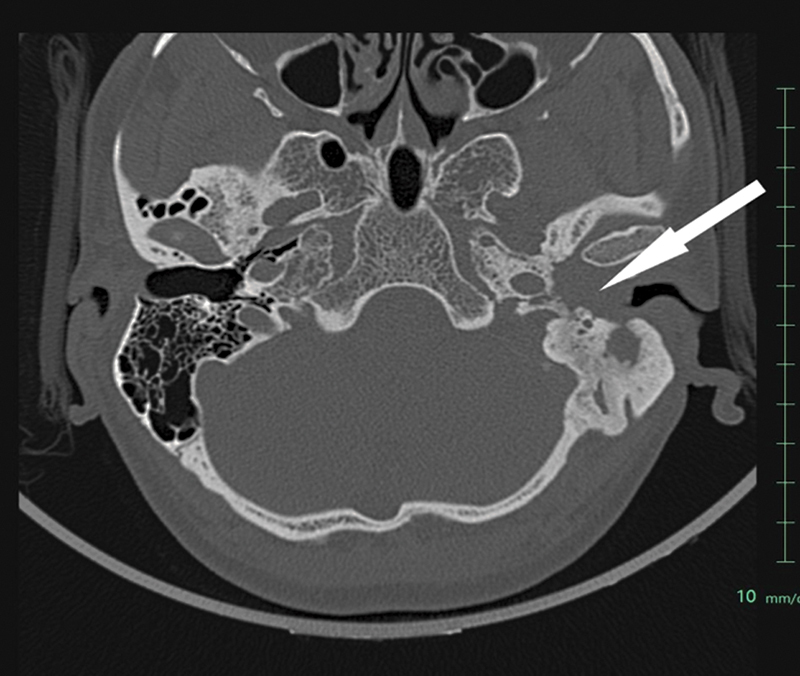

Neuroendocrine tumors of the middle ear are rare, comprising of less than 2% of primary tumors of the ear. The clinical and imaging findings of these tumors are nonspecific, and histological and immunohistochemical findings are confirmatory. Herein, we present a case of 48-year-old male, presenting with chief complaints of hearing loss of left ear with foul smelling discharge, with the initial clinical impression of otomastoiditis of the middle ear with cholesteatoma and being operated for the same, the final histopathology report inferred it as well-differentiated neuroendocrine tumor grade 1 with Ki-67 index less than 2%. Immunohistochemical examinations demonstrated positive staining of the tumor cells for cytokeratin, synaptophysin and chromogranin A, and negative for smooth muscle actin, desmin, S-100. The biochemical investigations showed raised serum chromogranin A levels. Based upon the findings on anatomical imaging modalities including high-resolution computed tomography temporal bone and magnetic resonance imaging paranasal sinuses (MRI PNS), the lesion was inferred inoperable due to involvement of dura of petrous apex, and therefore he was referred for consideration of peptide receptor radionuclide therapy (PRRT). MRI PNS also showed involvement of the horizontal part of facial nerve, indicating local aggressiveness of the tumor. 68 Ga-DOTATATE-PET/CT showed high-grade somatostatin receptor expressing soft tissue lesion involving middle ear and external auditory canal (Krenning's score 4), with low-grade metabolic activity on 18 F-FDG-PET/CT. The post-therapy scan following 177 Lu-DOTATATE PRRT, showed abnormal tracer concentration at the described site. Due to extreme rarity of this disease entity, it is important to accrue data for accurate diagnosis, proper management, and follow-up.